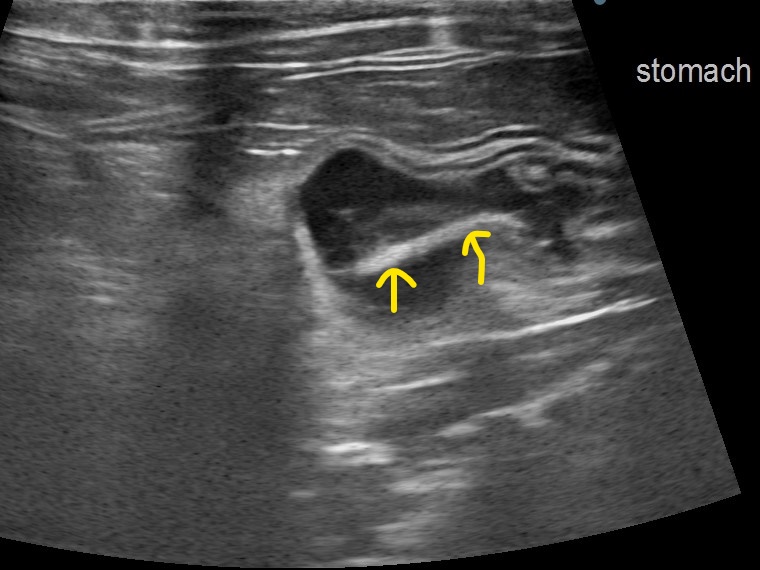

矢印:胃内のひも状異物